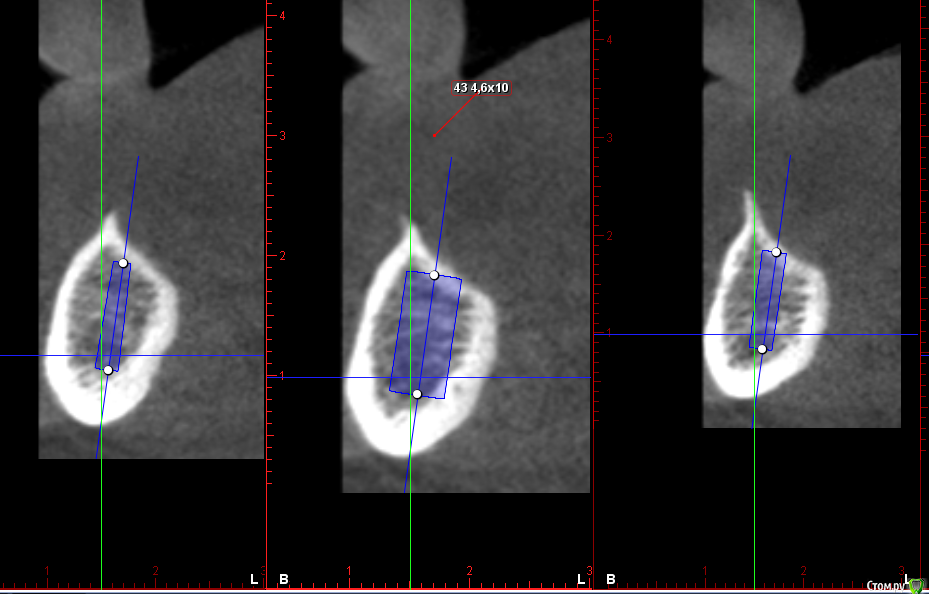

Sergiosse Опубликовано 2 марта, 2016 Поделиться Опубликовано 2 марта, 2016 Альвеолярный гребень полностью атрофирован.Во время отслойки показалось, что язычно отслаиваю мышцы.Показалось? Как лучше их отслаивать тупо или скальпелем? Впервые одномоментно ставил фдм, в обл 43 фдм короткий ( длиннее нет в наличии) и десна легла сверху ,ушивать не стал .Прорежется? .Тактика в таких случаях? заранее спасибо. Ссылка на комментарий